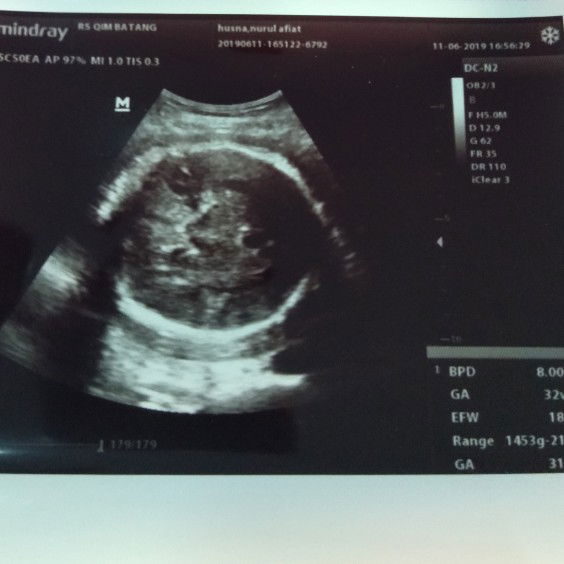

usg

berat anak saya kurang..sedih rasany hrsny ssi uk ini mlh berkurg 2w jd usia 32w dan rasany mkn g karuan bun dmarahi bojo jg ktny kl kyk gt kn jdny dsrh usg lg kn capek ngnterny astaghfirullah pdhl rncn nt usg lg uk 37 w eh ini dsrh blk 10 hr lg mhn doany y bun agar 10 hr kdepan udh ssi dg uk ny..aamiin